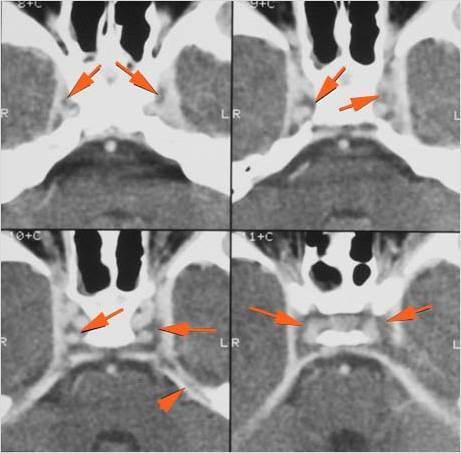

The extraocular muscles are swollen or otherwise abnormal. [Yes/No]

The intraconal orbital fat is infiltrated. [Yes/No]

The orbital apex and the superior and inferior orbital fissures are infiltrated. [Yes/No]

The superior and/or inferior ophthalmic veins are dilated or thrombosed. [Yes/No]